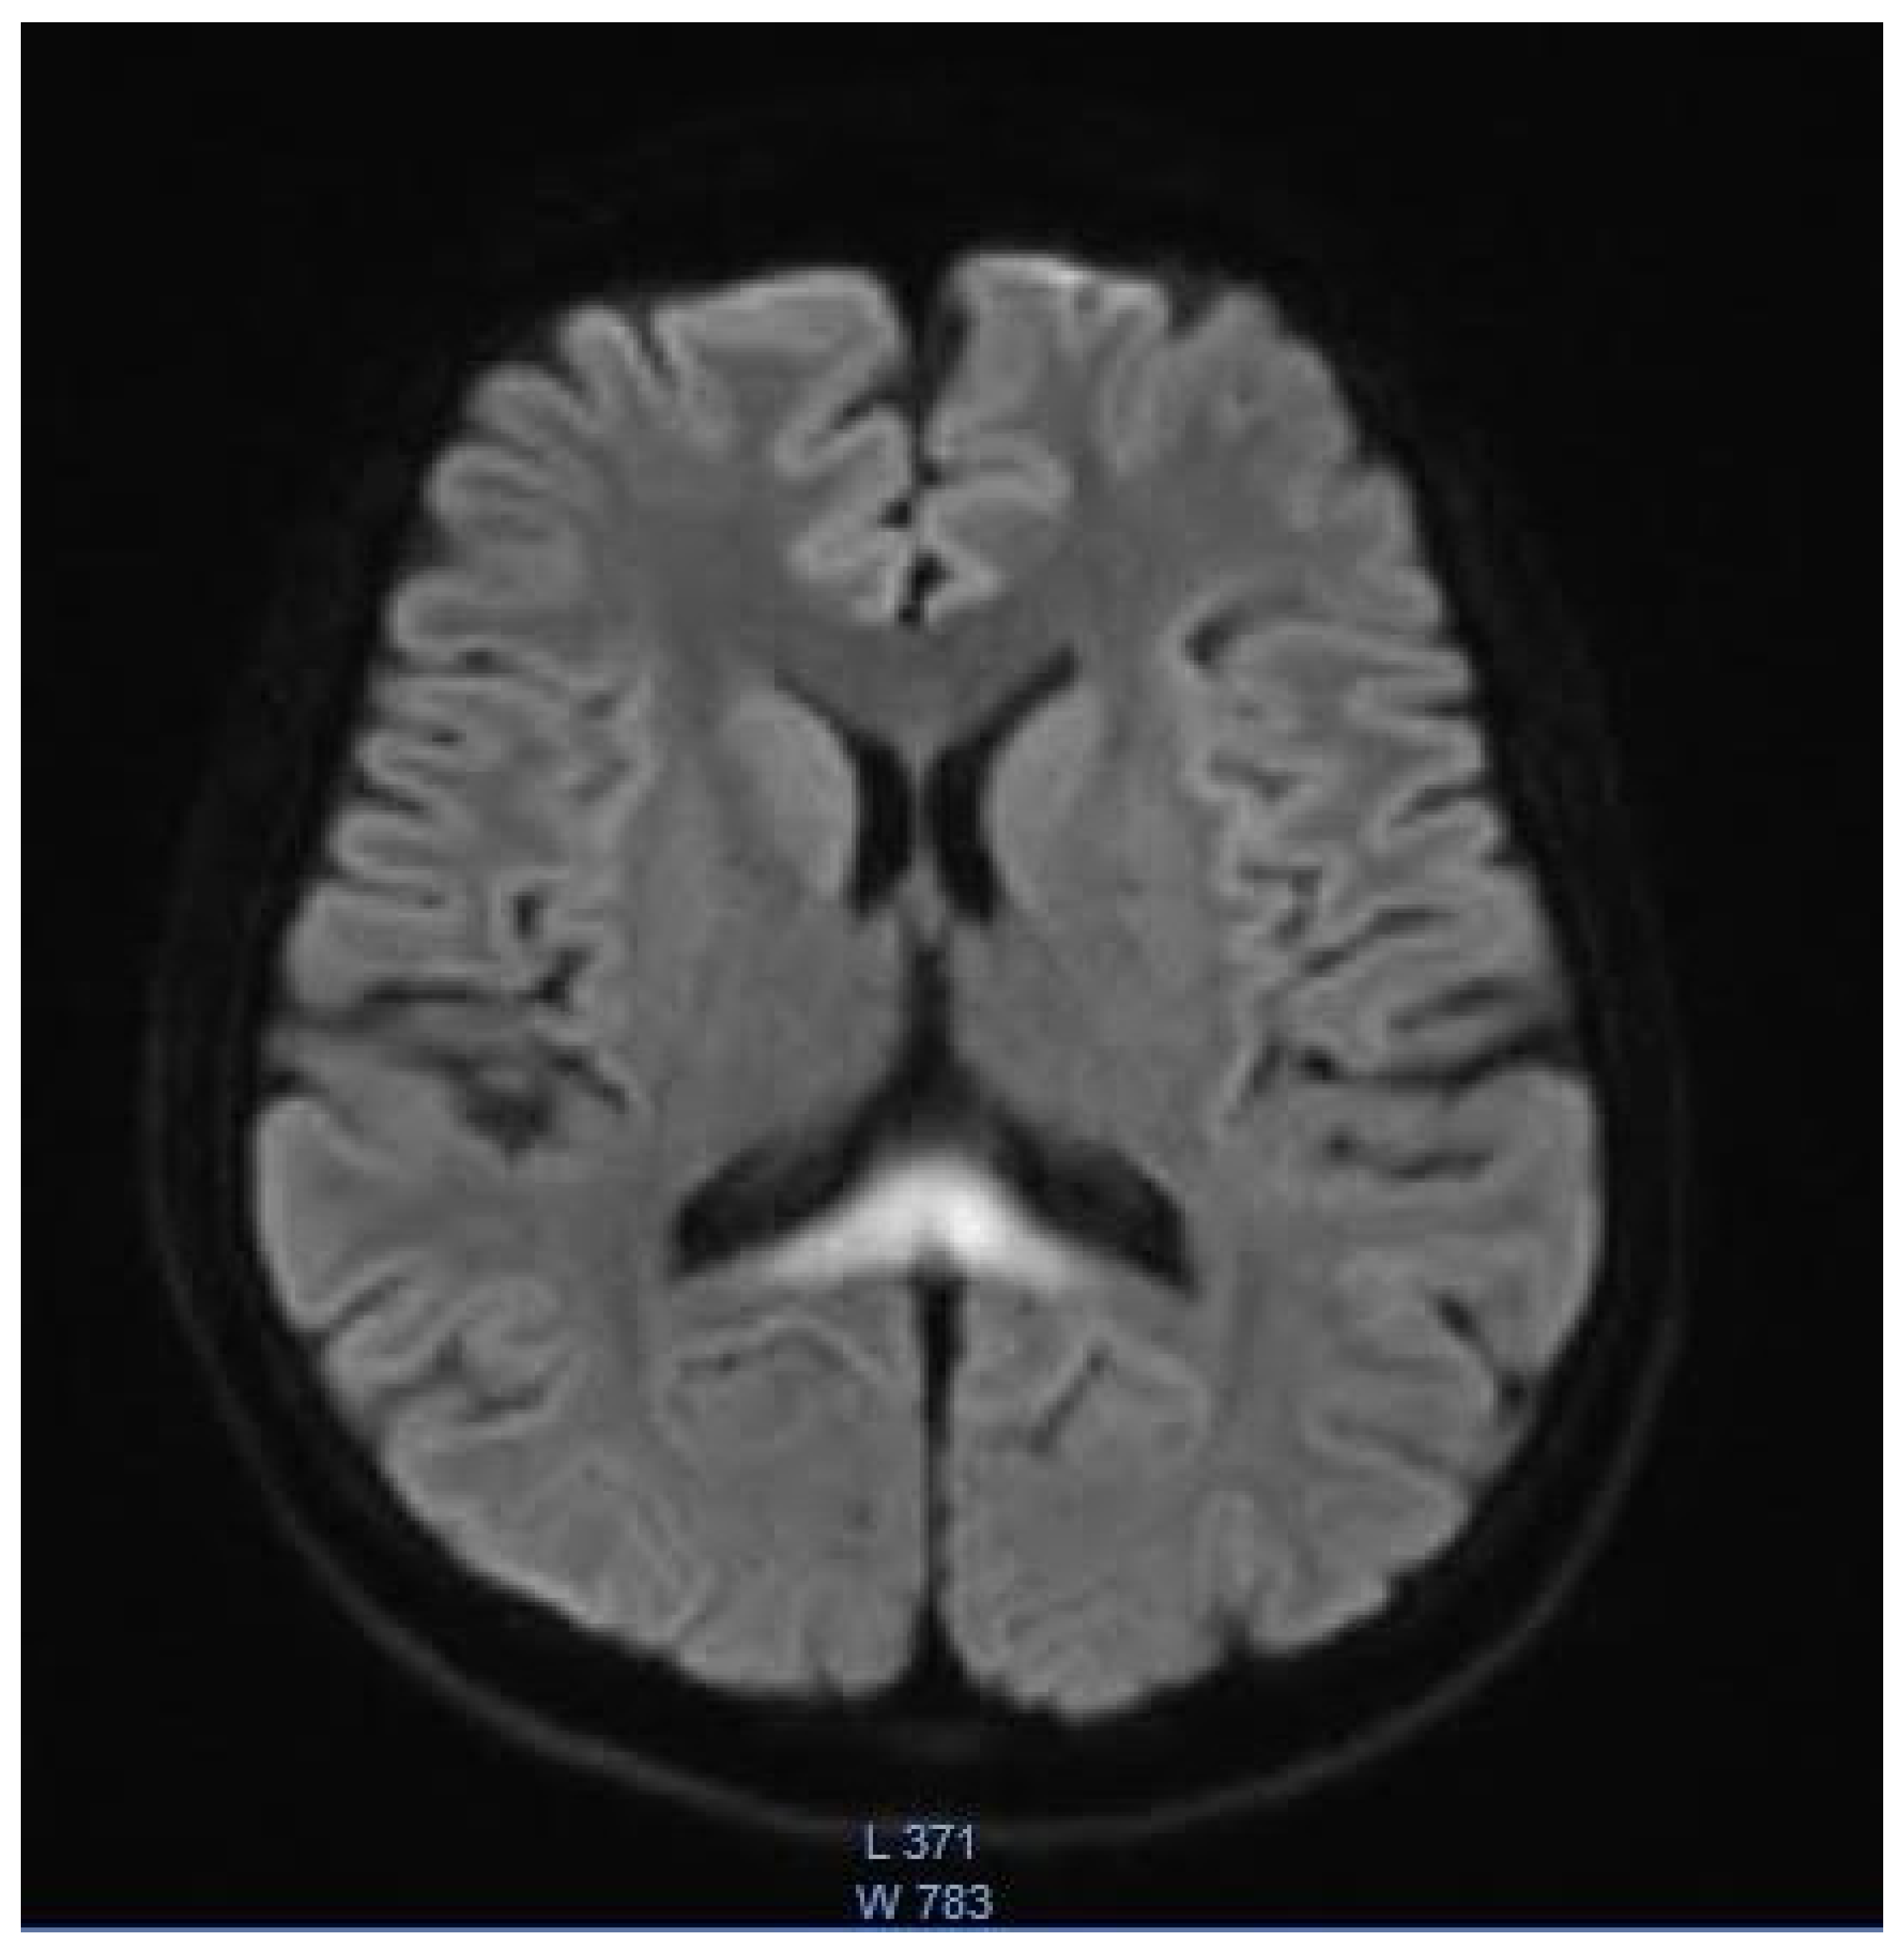

| Chang, 2021, USA [4] | 14, M | Clostridium difficile enterocolitis | N/A | N/A; N/A | Altered mental status; stiffening of 4 extremities; visual disturbance; slurred speech; gait instability | T2: symmetrical hyperintensity with corresponding diffusion restriction on DWI in posterior frontal, parietal, and occipital periventricular white matter and splenium of the corpus callosum | Near complete resolution | Near complete resolution |

| Gaye, USA, 2007 [6] | Teenager, M | appendectomy | N/A | N/A; N/A | Unresponsiveness; respiratory distress; decerebrate posturing | Left parietal flair signal | N/A | Resolution |

| Omrani, Iran, 2020 [8] | 11, M | Febrile bloody diarrhea | 12 g | N/A; N/A | Tinnitus; hearing loss; aggressive behavior; generalized dystonia; generalized tonic-clonic seizure; decreased level of consciousness. | T2: Symmetrical hyperintensity in dentate nuclei, substantia nigra, globus pallidi, splenium of the corpus callosum, and centrum semiovale | Improvement | Partial improvement |

| Sudan, 2016, India [11] | 14, M | Acute abdominal pain | N/A | 3; 5 | Dysarthria; altered mental status; seizures. | T2: symmetrical hyperintensity in the optic tracts, dorsal midbrain, inferior olivary nuclei, peri-aqueductal white matter, superior and inferior colliculi, superior cerebellar peduncle, dentate nuclei, medulla oblongata, and cervical spinal cord segment extending from the cervicomedullary junction to C6-C7 level DWI: restricted diffusion in the splenium of the corpus callosum | N/A | Resolution |